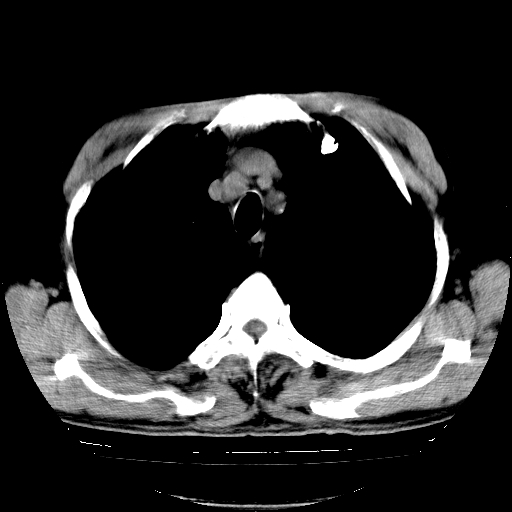

以下是引用hhcckk在2009-1-1 15:38:00的发言:[br]左下肺少许絮状模糊影--考虑感染[br]两肺散在小点状密度增高影--结合病史考虑矽肺?[br]气管壁钙化--可能由于老年退变性引起的